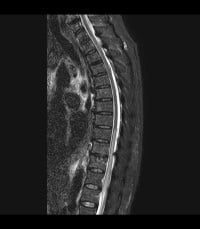

Reproduced from a case courtesy of Dr. Vincent Tatco, Radiopaedia.org, rID: 45707, these MRI images demonstrate changes seen in a different patient with spinal cord ischemia due to aortic dissection. The sagittal views of T2-weighted and STIR sequences reveal a pencil-shaped area of increased signal in the intramedullary spinal cord from T8-T9 to the conus medullaris. The axial views of T2-weighted MRIs may exhibit an owl’s eye appearance where the patient has high signals in the anterior horn cells bilaterally.